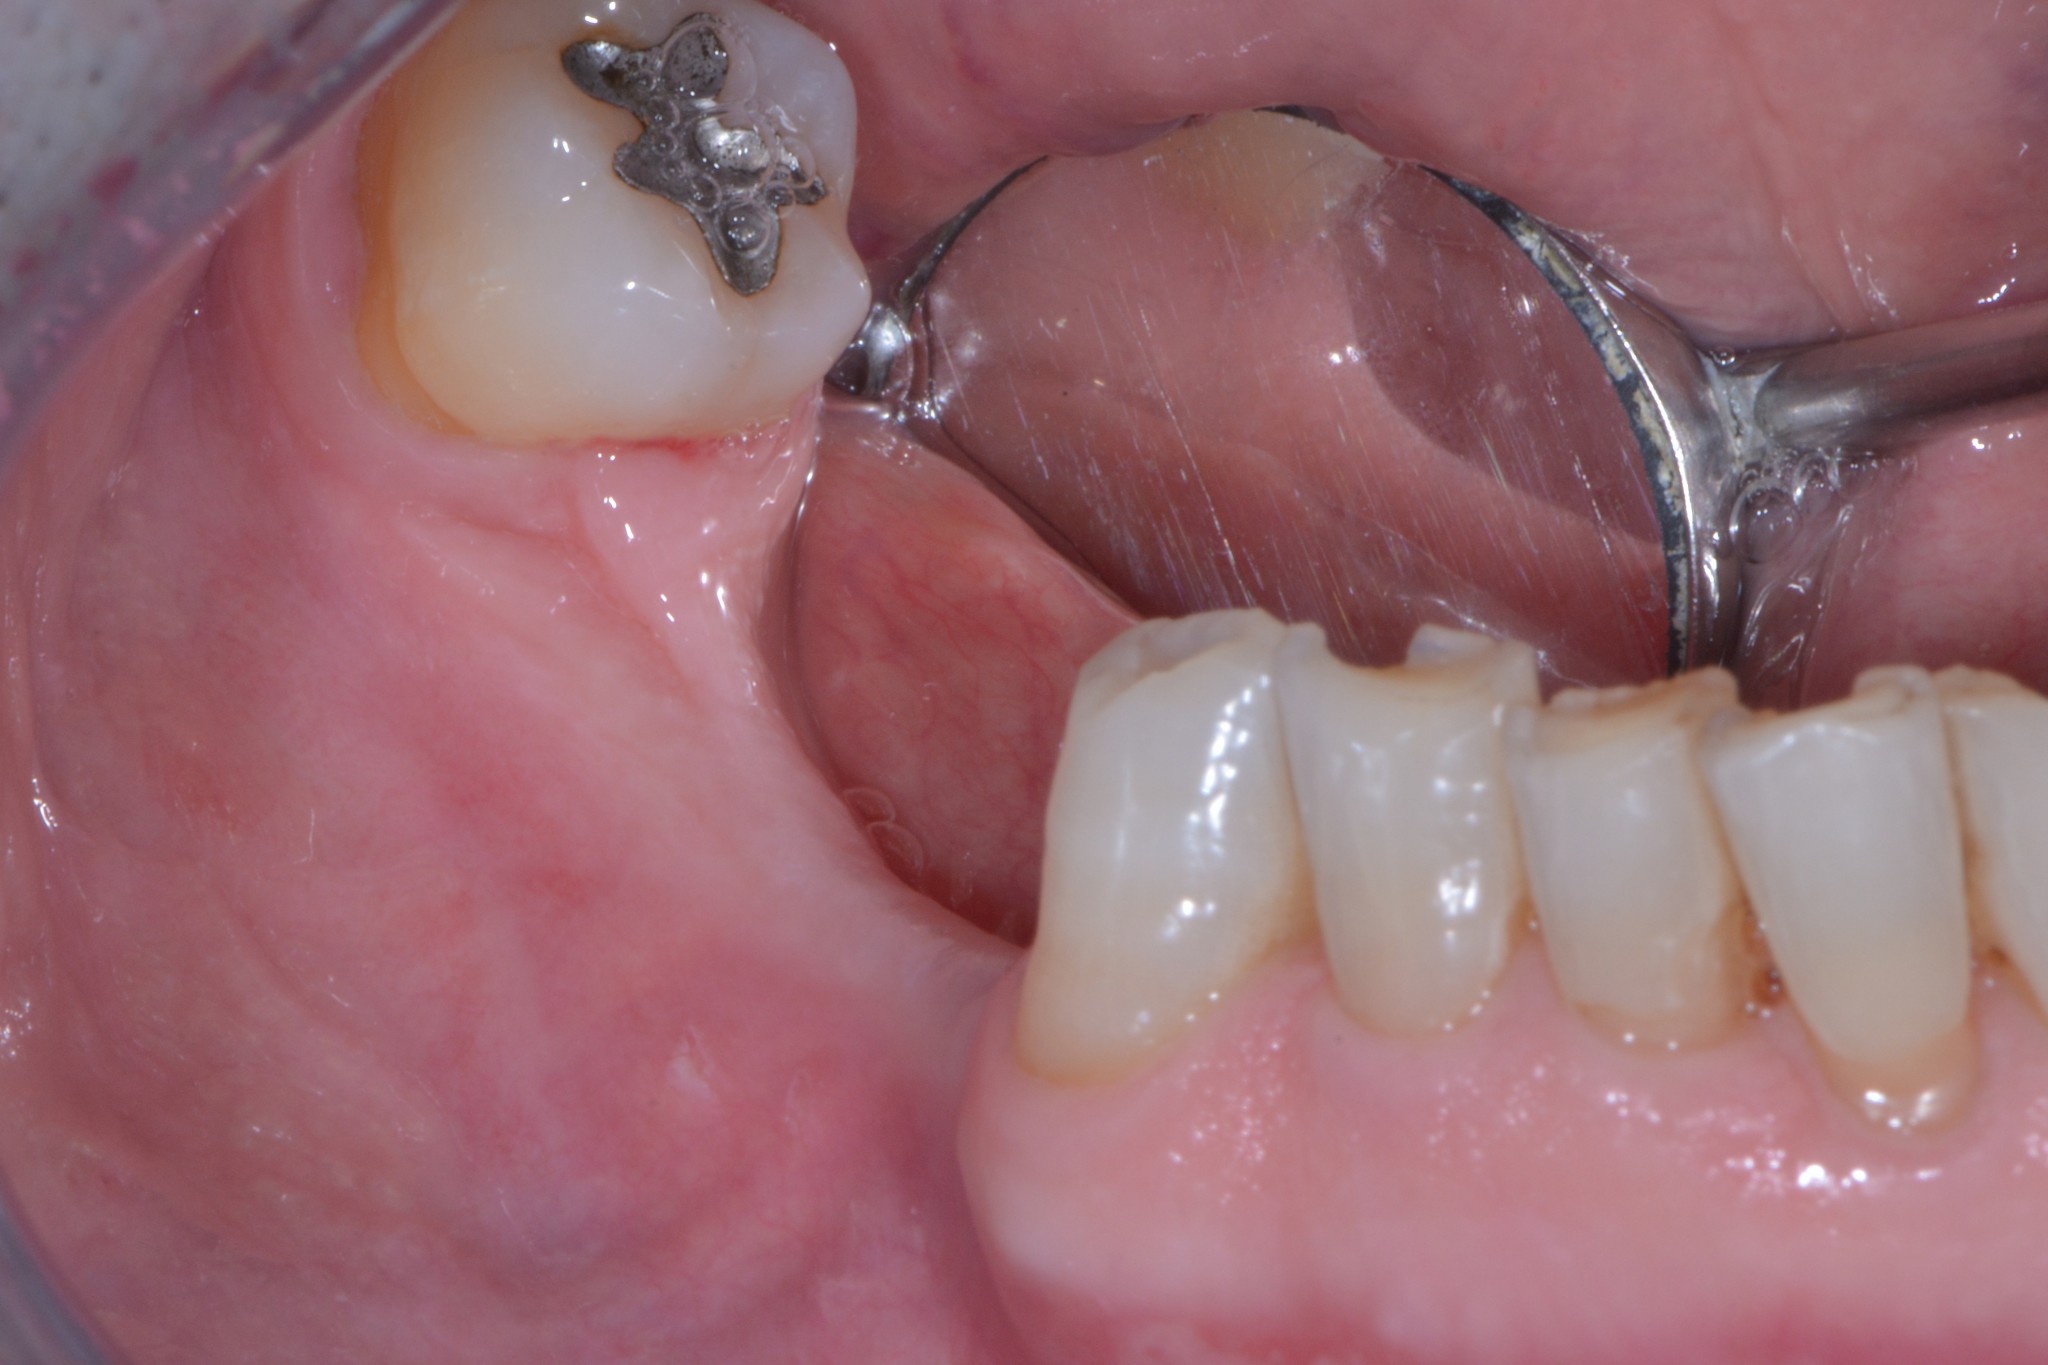

Il signor Franco, nostro paziente da quasi dieci anni, qualche mese fa ha finalmente deciso di mettere gli impianti che gli avevamo proposto nel lontano 2007. Già dalla foto dovresti notare una marcata atrofia verticale e orizzontale. Come mio solito faccio fare una radiografia tridimensionale per progettare l’intervento in sicurezza e spiegare al paziente esattamente cosa andrò a fare durante la seduta chirurgica…

Cosa vedi? Ok, una bella atrofia orizzontale, associata ad una modesta atrofia verticale. Come possiamo trattare una atrofia verticale associata ad una orizzontale? (rimanendo all’interno dell’evidence based medicine per carità!)

Te lo dico io: GBR (con vari tipi di barriere) o innesti a blocco. Io utilizzo entrambe le tecniche ma in questo caso, per una serie di motivi che forse un giorno discuteremo, ho optato per l’innesto a blocco.

Hai guardato bene le immagini? Possiamo partire? BISTURI!!

Avevi notato questo? Dai tagli della cone-beam si nota chiaramente una variante anatomica abbastanza importante: un foro mentoniero accessorio posizionato più o meno a metà tra la cresta e il foro primario, diciamo circa 7 mm apicalmente alla cresta, dal quale emerge un ramo di diametro rilevante del nervo alveolare inferiore. Chissà a quale parte del mento o del labbro porta le sensibilità quel piccolo ramo!? Diciamo che per mantenere immacolato il mio palmares medico legale preferisco non scoprirlo!

Solo adesso che il caso ci è ben chiaro possiamo iniziare il nostro intervento avendo le idee ben chiare, un paziente ben informato e una buona probabilità di non fare cazzate.